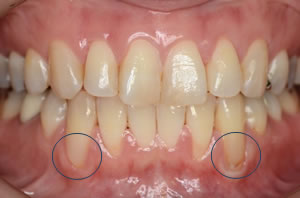

『歯肉退縮』は、歯根が露出し“知覚過敏”が引き起こされる、“歯面が楔状に欠損”してしまうなどの問題が起こる事があり、特に問題となるのは前歯です。審美性が重要視される前歯部においての歯肉退縮は、歯肉のラインが不規則になり“審美的に大きな問題”となるからです。その対処法として、結合組織移植術による根面被覆治療があります。

青丸が歯肉退縮しています。 |